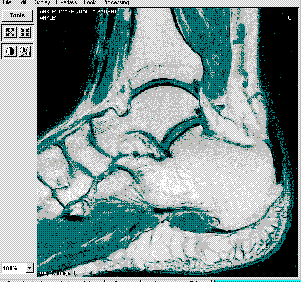

Figura 1. Ejemplo de aplicación de visualización sobre

PC

La visualización de imágenes DICOM no plantea problemas significativos, pudiendo emplearse para ello simplemente un ordenador personal. La Figura 1 muestra un ejemplo de aplicación visualizadora sobre un PC. No obstante, podemos destacar que nuestro sistema utilizará un navegador Internet como puerta de acceso y de visualización de los datos, como se comenta en una sección posterior.